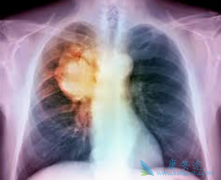

肺癌是我国恶性肿瘤头号杀手,发病率和死亡率均位居第一。据2015年数据统计,我国肺癌新发病例超过73万,其中非小细胞肺癌占85%,多数肺癌患者确诊即为晚期,严重影响预后及生存。作为第二代口服小分子EGFR TKI,阿法替尼( AFATINIB )具有独特的作用机 ...